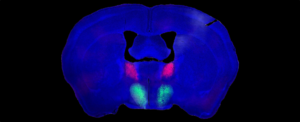

Зображення мозку самця миші, з BNST рожевим кольором і преоптичним гіпоталамусом зеленим. Імпульс проходить від рожевого до зеленого в нейронному ланцюзі, що керує шлюбним потягом, поведінкою та задоволенням. (Деніел Бейлесс/Станфорд)

Одна група генетично відмінних нейронів BNST виробляє пептид, відомий як субстанція P, повідомляють дослідники, в той час як інша унікальна група нейронів преоптичного гіпоталамуса має рецептори субстанції P.

Нейрони BNST, що виробляють субстанцію P, сформували зв’язки зі своїми рецептивними аналогами з преоптичного гіпоталамуса, і вони виявили принаймні одну мету, якій ці зв’язки можуть слугувати.